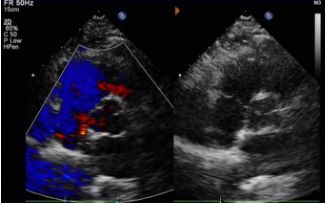

Day 1 to 9 Months:

No residual shunt observed.

Gradual reduction in device echogenicity.